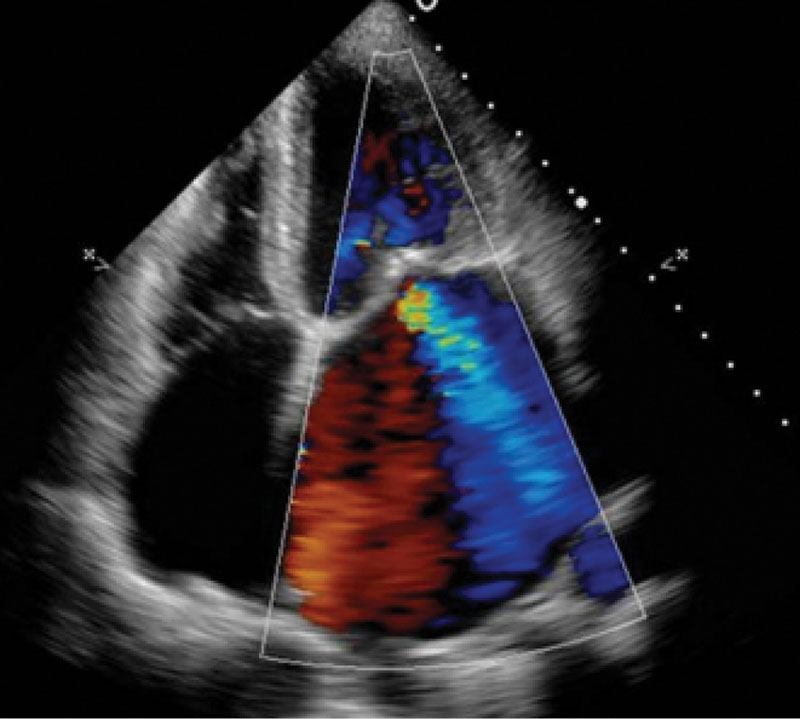

Рис. 2. Магнитно-резонансная томография сердца с внутривенным контрастированием на момент поступления: фиброз миокарда левого желудочка в базальных, средних и верхушечных отделах

По данным ЭхоКГ: отмечается фиброз створок митрального клапана, отрыв хорд задней створки митрального клапана с формированием регургитации 3-й степени (рис. 1), фиброз створок легочного клапана, пиковое давление в стволе легочной артерии – 50 мм рт. ст., фиброз створок аортального и трикуспидального клапанов без нарушения гемодинамики, отмечается дилатация полости левого предсердия – до 97 мл, объемы левого желудочка (ЛЖ) – в пределах нормы, локальная сократимость и глобальная функция ЛЖ – не нарушены, фракция выброса – 66%, диастолическая дисфункция ЛЖ 2-го типа, объемы правых камер сердца – не увеличены. По результатам селективной коронарной ангиографии, гемодинамически значимого поражения коронарных артерий не выявлено. В качестве дообследования выполнена магнитно-резонансная томография сердца с внутривенным контрастированием, по результатам которой выявлен протяженный фиброз миокарда ЛЖ в базальных, средних и верхушечных отделах – суммарно 6,8% (рис. 2).